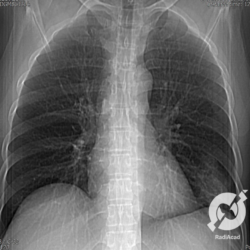

Os agentes etiológicos infecciosos são variados (bactérias, vírus, fungos, parasitas…), mas o que ocorre nos pulmões durante uma infecção por qualquer tipo de agente é a substituição do ar alveolar por secreção (pus, muco, eventualmente sangue ou necrose…) e com isso a manifestação radiográfica vai ser a mesma já que todas estas secreções apresentam a mesma densidade radiográfica: partes moles.

E o nome dado a esta alteração radiográfica que corresponde à substituição do ar alveolar por líquido é a consolidação alveolar.

Uma consolidação alveolar é, por definição, uma opacidade (imagem densa, branquinha) homogênea ou às vezes heterogênea (pela presença de calcificações ou cavidades), de limites mal definidos, exceto quando toca a pleura da parede ou das cissuras pulmonares. É um termo usado tanto em radiografia, como em tomografia computadorizada. Na tomografia, um outro termo é usado: vidro fosco, que é uma opacidade (branquinha mas não tanto como a consolidação), que borra o pulmão mas deixa ver os vasos de permeio (igual bigode de adolescente: dá pra ver todo o fundo).

Nós vamos mostrar aqui um pequeno apanhado de pneumonias de variados agentes, em diversos segmentos e lobos pulmonares, com extensões variadas. O objetivo é identificar o padrão radiológico de consolidação alveolar e não determinar o agente infeccioso, isso vai ser assunto para mais adiante. Aliás já antecipo que é fundamental saber localizar a lesão, porque alguns destes bichos gostam de determinados segmentos, alguns tumores também têm as suas preferências, então localização é fundamental. Se localização não fosse importante, um apartamento na beira do mar sairia o mesmo preço de um apartamento de frente pra BR-101, concordam?

Seguem alguns dos nossos casos de pneumonia para vocês treinarem os olhos e não se apavorarem nos plantões.